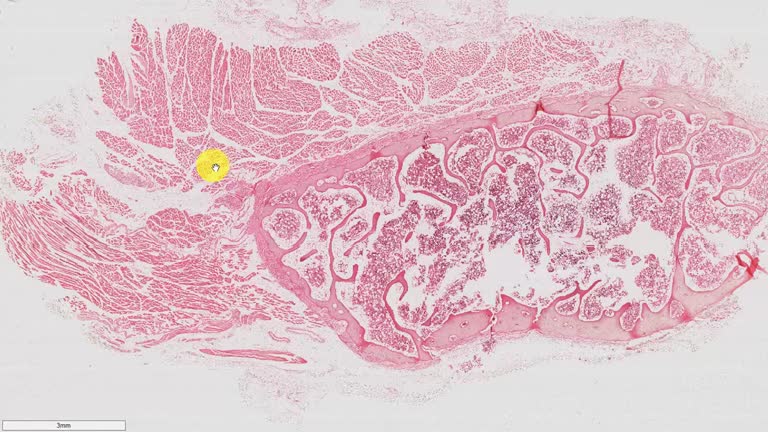

Práctica 01 - Preparación 1 - Paladar blando